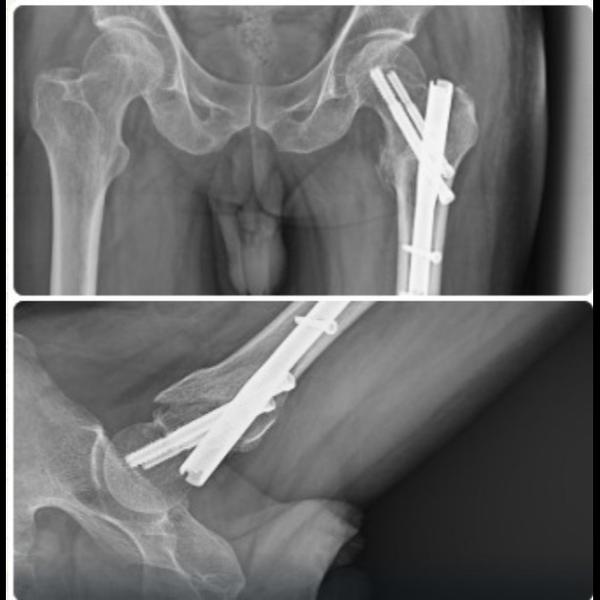

TFN fixation for Intertrochanteric fracture !